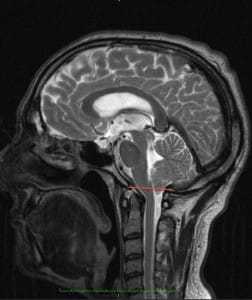

Следует отметить, что МСКТ и КТ головного мозга при хорошей визуализации костных структур краниовертебрального перехода не позволяют достаточно точно судить о мягкотканных образованиях задней черепной ямки. Поэтому единственным достоверным методом диагностики аномалии Киари на сегодняшний день является магнитно-резонансная томография. Ее проведение требует обездвиженности пациента, поэтому у маленьких детей она проводится в состоянии медикаментозного сна. Кроме МРТ головного мозга для выявления менингоцеле и сирингомиелических кист необходимо также проведение МРТ позвоночника, особенно его шейного и грудного отделов. При этом проведение МРТ исследований должно быть направлено не только на диагностику аномалии Киари, но и на поиск других аномалий развития нервной системы, которые часто с ней сочетаются.

Точная диагностика аномалии стала возможна благодаря использованию МРТ, посредством которой врач может определить и костные пороки, и варианты развития самого мозга, его сосудов, уровень расположения отделов относительно черепных костей, их размеры, объем задней черепной ямки и ширину большого затылочного отверстия. МРТ можно считать единственным точным и самым достоверным методом выявления патологии.

МРТ требует обездвиживания пациента, который должен какое-то время спокойно лежать на столе аппарата. У детей с этим могут возникнуть значительные трудности, поэтому исследование проводят в состоянии медикаментозного сна. Для поиска сочетанных пороков спинного мозга и позвоночника исследуют также эти отделы позвоночного столба.